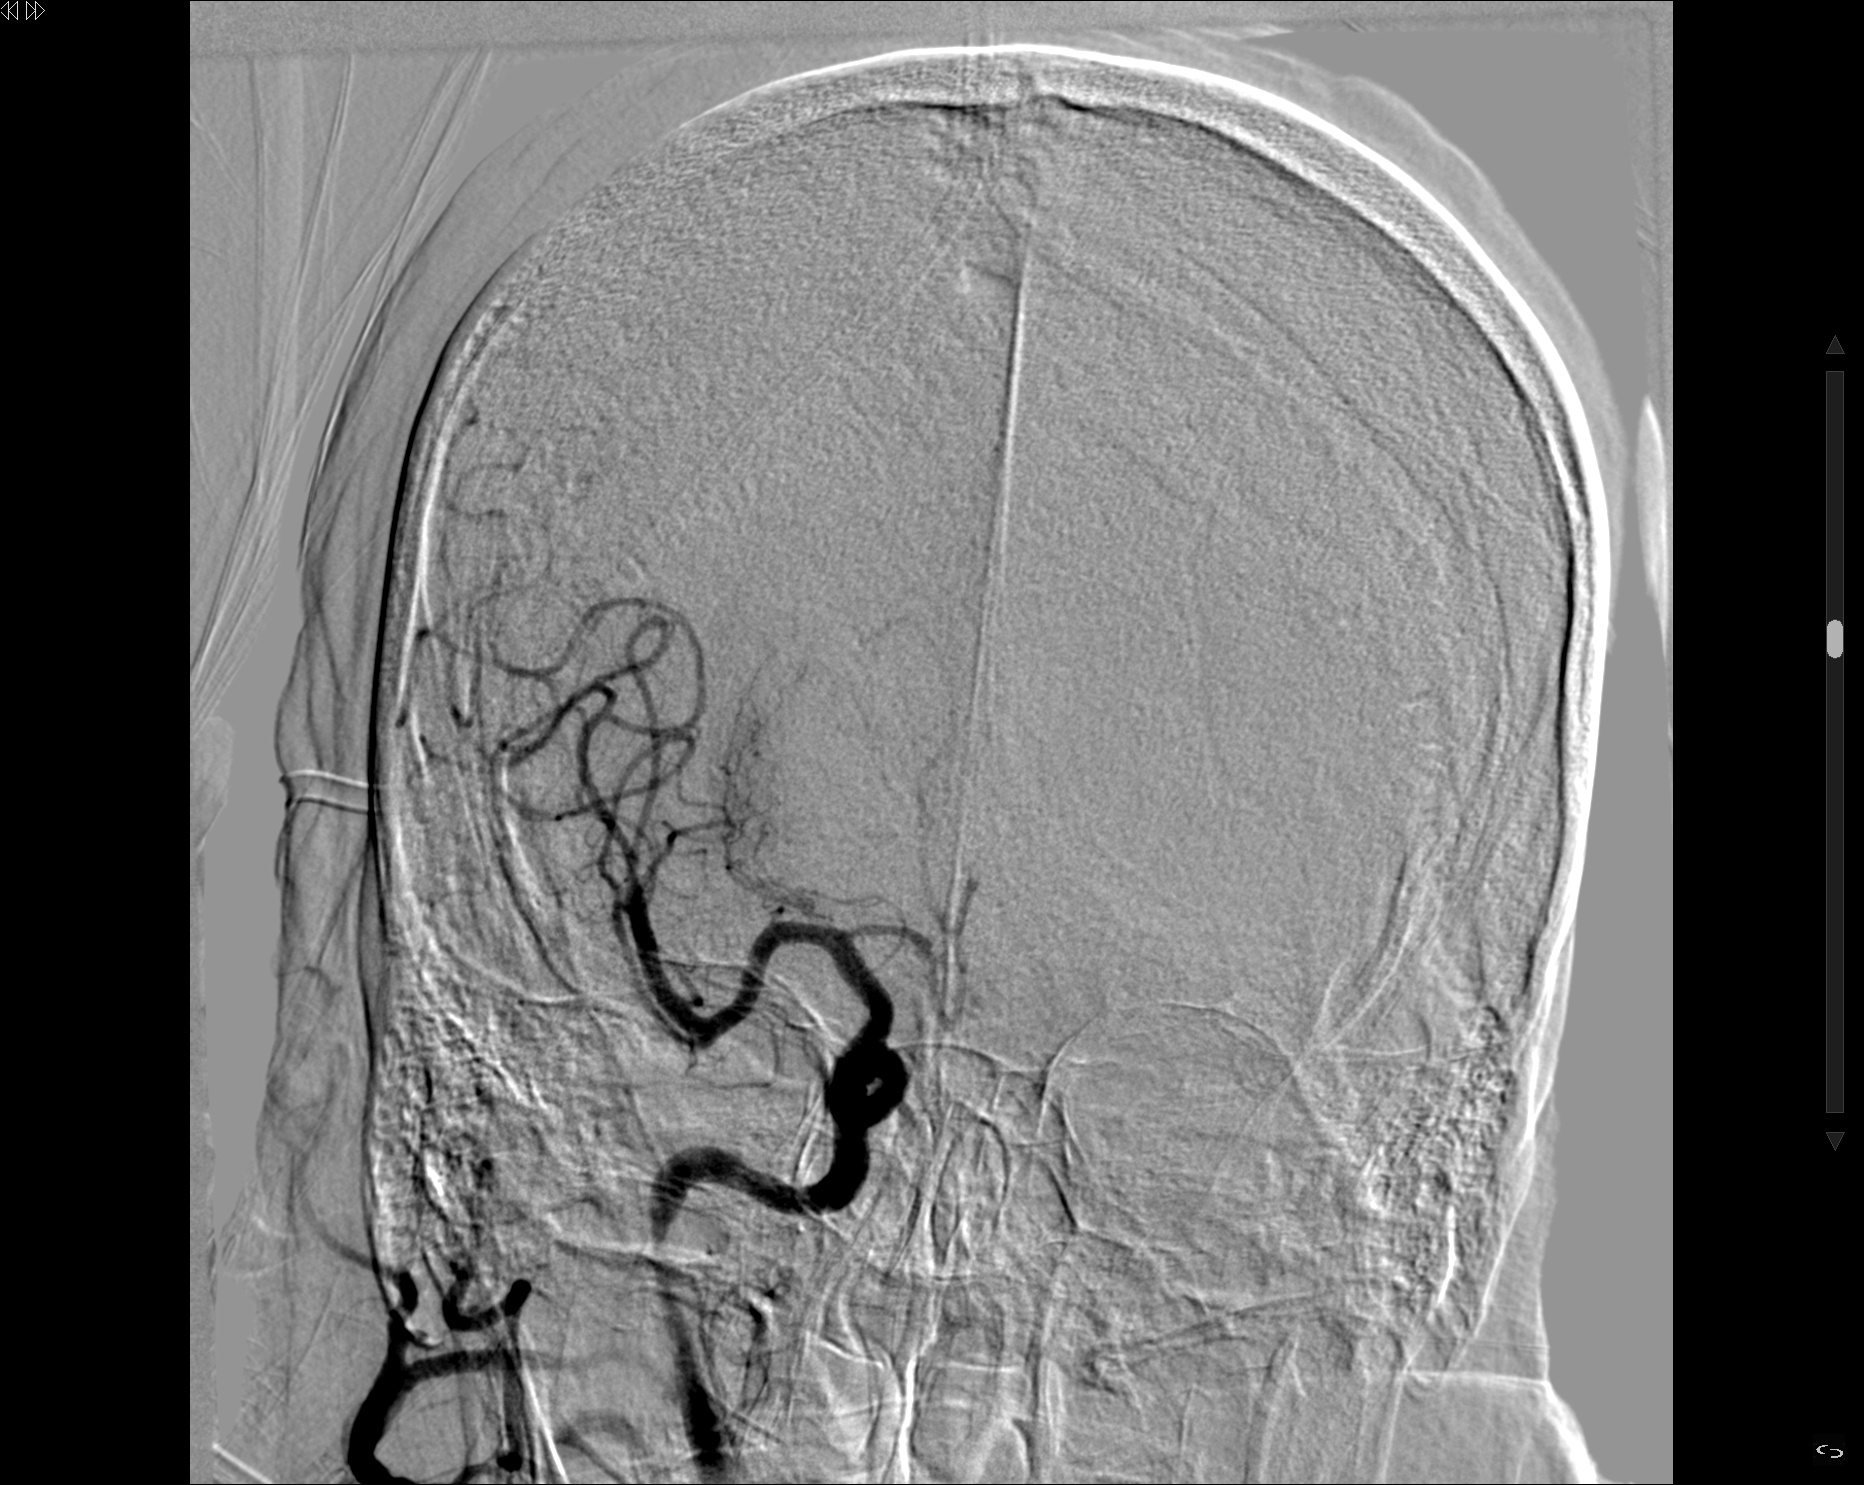

Se decide colocación de STENT en carotida interna

Comparativa pre y postratamiento utilizando la herramienta IFLOW